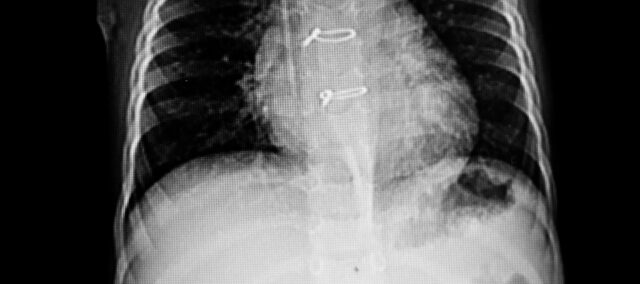

Ensisijainen tulos oli rintalastan irtoaminen ultraäänellä mitattuna. Rintalastan kahden puoliskon välinen etäisyys määritettiin ja suurin ero merkittiin. Toissijaisena tuloksena käytettiin rintalastan instabiliteettiasteikkoa, jossa arvioidaan rintalastan eheyttä asteesta 0 (kliinisesti vakaa rintalasta) asteeseen 3 (huomattava liike tai irtoaminen). Mittaukset tehtiin lähtötilanteessa (7. leikkauksen jälkeinen päivä) ja viikolla 4.

Mukaan otettiin 36 naista, joilla oli ultraäänellä vahvistettu akuutti rintalastan instabiliteetti. Lähtötilanteen ominaisuudet osoittivat kaksi vertailukelpoista ryhmää. Heillä oli lähtötilanteessa 0,23 cm:n rintalastan erotus...

Ensisijainen tulos, rintalastan irtoaminen viikolla 4, oli 0,13 cm koeryhmässä ja 0,22 cm kontrolliryhmässä. Ryhmien välinen ero oli -0,09 cm (95 % CI 0,07-0,11) sen hyväksi, että interventioryhmä suoritti vartaloa stabiloivia harjoituksia sternotomian jälkeen.